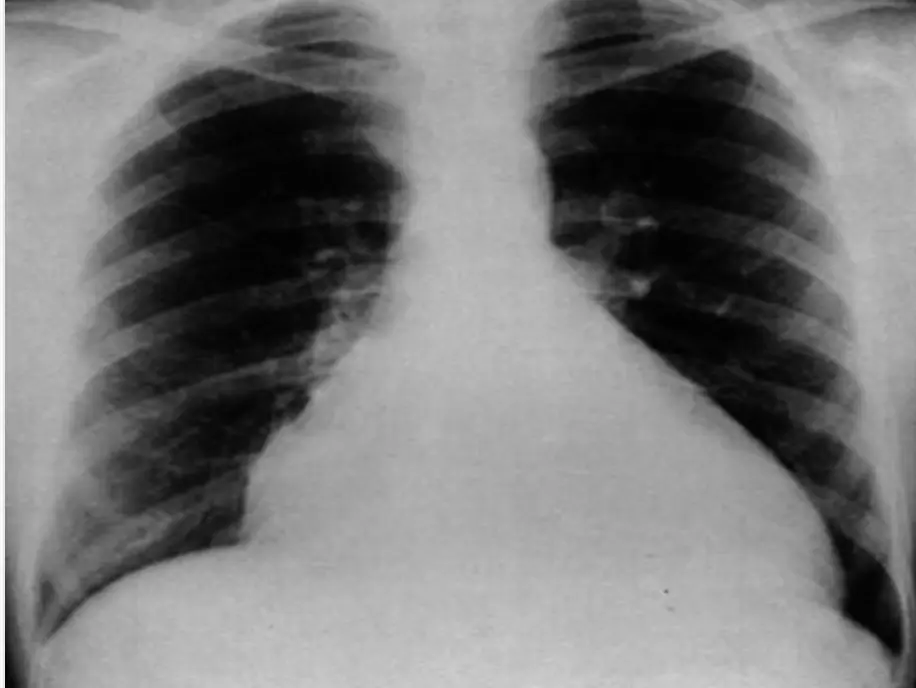

Chest Radiography

- Cardiomegaly: Left-to-right shunting defects, Dilated cardiomyopathy, Myocarditis, and Pericardial effusion.

- Pulmonary congestion/pulmonary edema.

- Pleural effusion.

- Pericardial effusion.

Chest radiograph of a 13-year-old boy with dilated cardiomyopathy